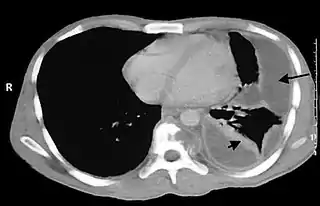

![]() Empiema pleural en tórax. | ||

- en la cavidad pleural (empiema pleural, también conocido como piotórax)

- en la cavidad torácica